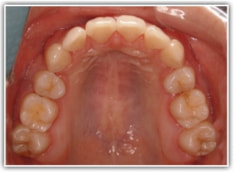

治療前

治療開始時

上下顎とも前突しており、叢生もあります。分析値からも抜歯対象症例です。